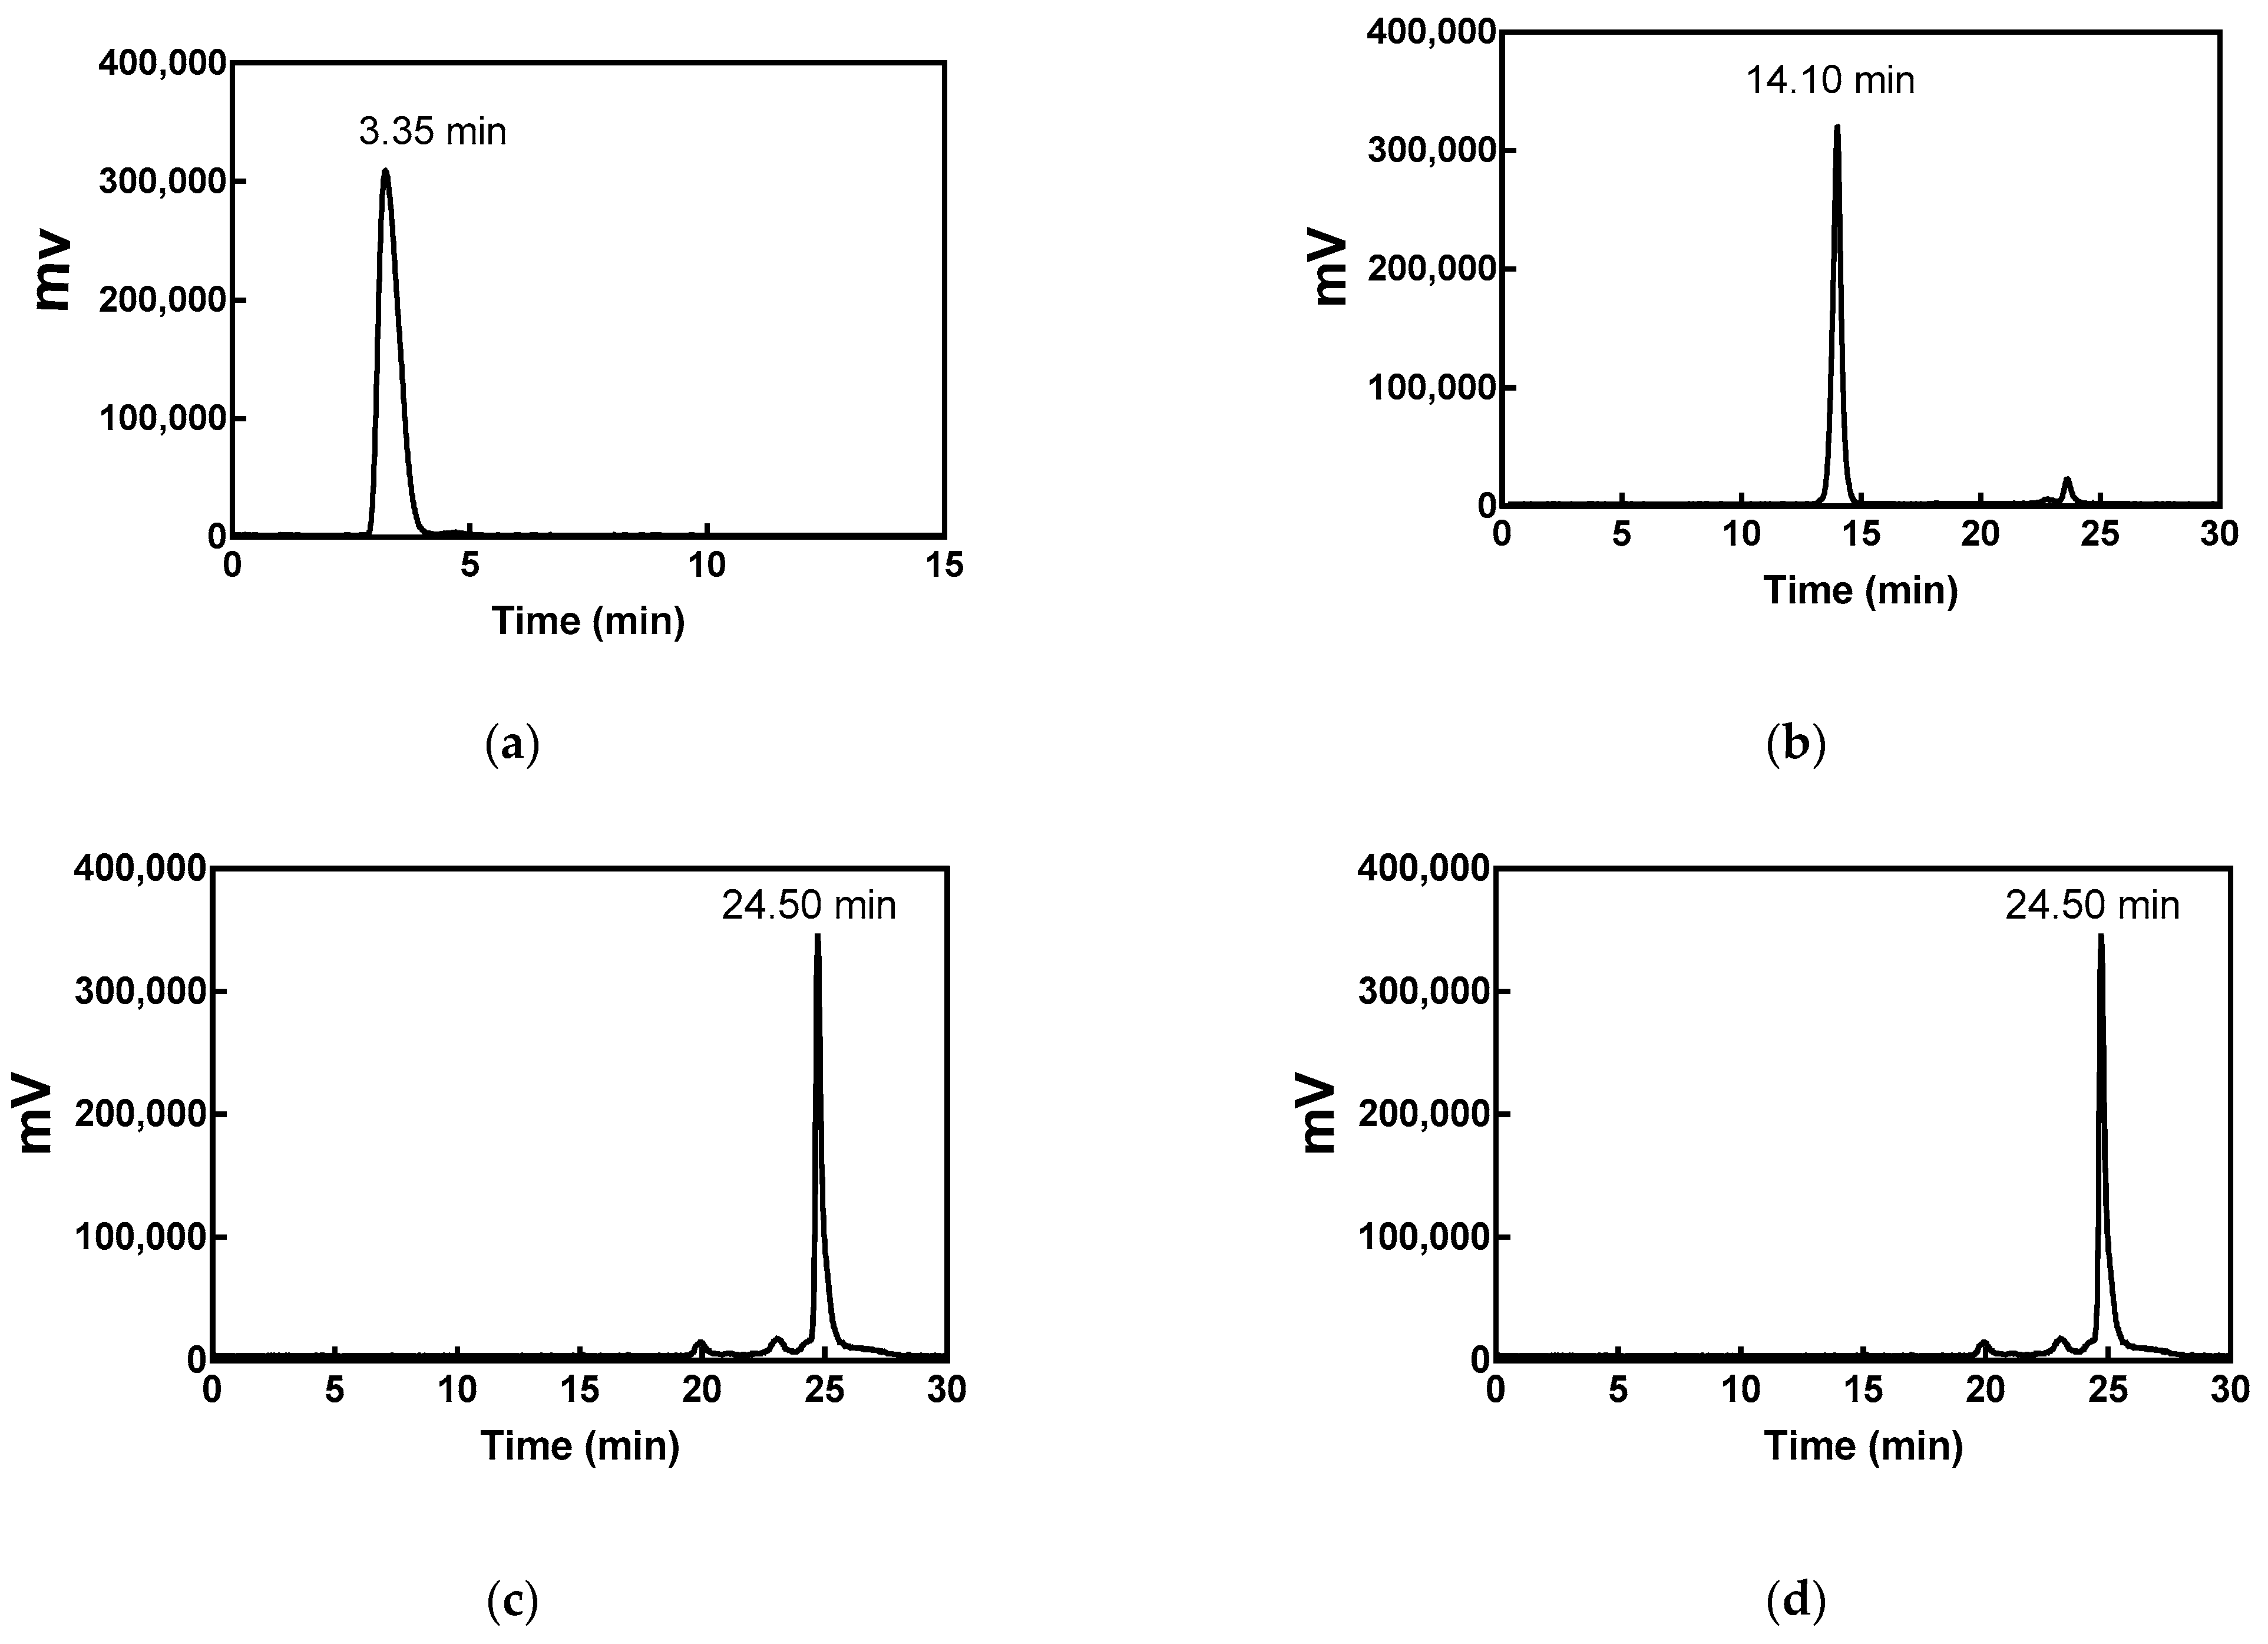

2.2. Radiolabeling and Quality Control

4.3. Radiolabeling and Quality Control